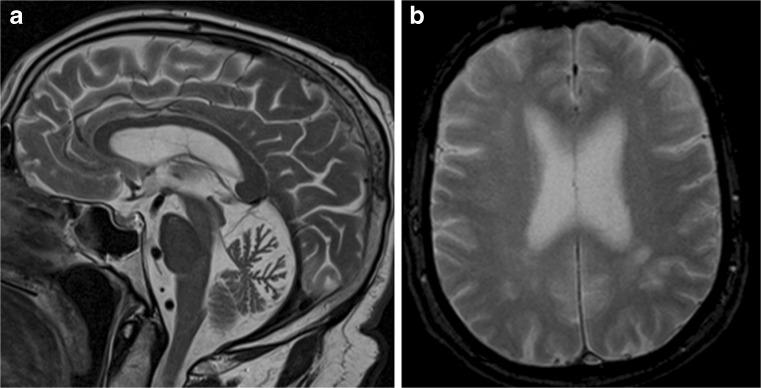

Structural Brain Imaging and [18F] FDG PET

The imaging data are summarized in Table 1 and are shown in Figs. 2, 3, 4, 5, 6, 7, and 8. Brain MRI revealed atrophy of the vermis and supratentorial white matter hyperintensities (WMH) in patients III:1 and III:2 and to a lesser degree in the index case (Figs. 2, 3, and 5). These WMH were particularly widespread in III:1 (Fig. 2). The index case was not affected by any other comorbidity usually associated with WMH, suggesting that these abnormalities may be an underlying feature of SCA19/22. WMH were not evident in the youngest patient (V:1). [18F] FDG PET revealed hypometabolism in the entire cerebellum, thalamus, prefrontal cortex (PFC), and parietal regions of the index case (IV:1) (Fig. 6). Her mother had reduced glucose metabolism not only in the PFC but also in the vermis as wells as in the motor and temporal cortex (Fig. 4). The youngest patient (V:1) had hypometabolism in the PFC, parietal, and inferior temporal regions but surprisingly not in the cerebellum (Fig. 8). In the latter structure, atrophy of the vermis was evident (Fig. 7).

Fig. 2.

Brain MRI of patient III:1. a Midsagittal T2-weighted image displays moderate vermis atrophy. b Coronal T2-weighted image showing periventricular and deep white matter hyperintensities